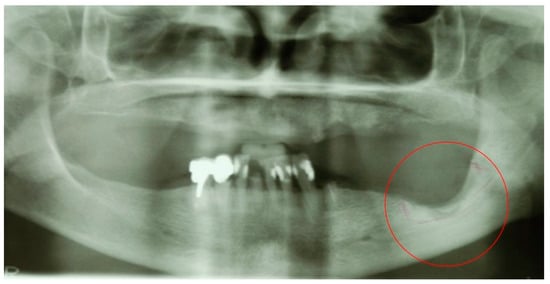

5.2. Case Report 2

A 65-year-old female patient developed MRONJ after the administration of intravenous DB. The lesion has been radiologically identified through OPT and is located in teeth 36–38 (Figure 13).

Figure 13.

OPT of initial lesion pointed by the circle.